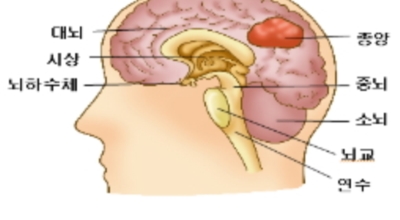

뇌종양이란 뇌 조직이나 뇌를 싸고 있는 막에서 발생한 종양과, 머리뼈나 주변 구조물로부터 멀리 떨어진 부위에서 뇌 조직이나 뇌막으로 전이된 종양을 의미해요. 뇌종양은 양성과 악성으로 나눌 수 있습니다. 양성 뇌종양은 성장 속도가 느리며 주위 조직과의 경계가 뚜렷해요. 양성 뇌종양은 수술 이외의 다른 치료 없이 완치되는 경우가 흔하고, 대부분 천천히 자라기 때문에 수술하지 않고 경과를 관찰하기도 해요. 그러나 양성 뇌종양도 완치될 수 없는 경우가 있습니다.

뇌간이나 척수와 같은 특정 부위에 발생된 종양은 수술로 없앨 수 없습니다. 또 크기가 작더라도 생명에 중요시되는 기능을 담당하는 뇌와 척수에 정도가 심한 훼손을 입힐 수 있답니다. 이 경우 조직학적으로는 양성이지만, 임상적으로는 악성과 같습니다. 악성 뇌종양은 뇌암이라고도 하고, 성장 속도가 빠르며 주위 조직으로의 침투 역량이 강해요. 이에 따라 정상 뇌 조직으로 침윤되고 정상 뇌 조직과의 경계가 불분명해서 치료가 어려운 편이예요. 악성 뇌종양은 주변의 정상 뇌 조직을 빠른 속도로 파괴해요.